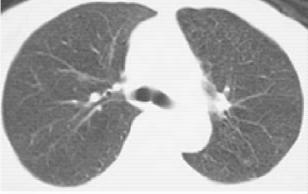

图1-2 男性,44岁,咯血1个月,浸润型肺结核

浸润型肺结核多见于成年人,起病缓慢,临床症状视其病灶范围及人体反应性而定。早期及病灶较小者往往无明显症状及体征,常由健康查体时的胸部X线检查发现,显示为锁骨上下片状、絮状阴影,边缘模糊。当人体处于过敏状态且有大量结核菌进入肺部时,病灶呈干酪样坏死、液化,进而形成空洞及病灶的支气管播散(图1-2)。浸润型肺结核伴大片干酪样坏死灶时,常呈急性进展,出现严重毒性症状,临床上称为干酪性(或结核性)肺炎。干酪样坏死灶部分消散后,周围形成纤维包膜;或空洞的引流支气管阻塞,致使空洞内干酪物难以排出,凝成球形病灶,称为“结核球”(图1-3)。当病变处于炎症渗出、细胞浸润甚至干酪样坏死阶段,经恰当的抗结核化学治疗后,炎症吸收消散;遗留的细小干酪样病灶经纤维包围,逐渐失水、干燥甚至钙化,成为残留的结节状病灶,称纤维硬结病灶或临床痊愈。